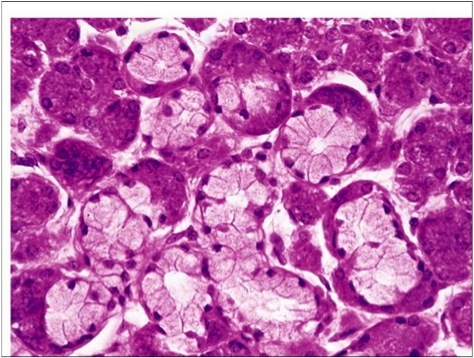

What type of cells are found in the mouth?

Stratified Squamous epithealium